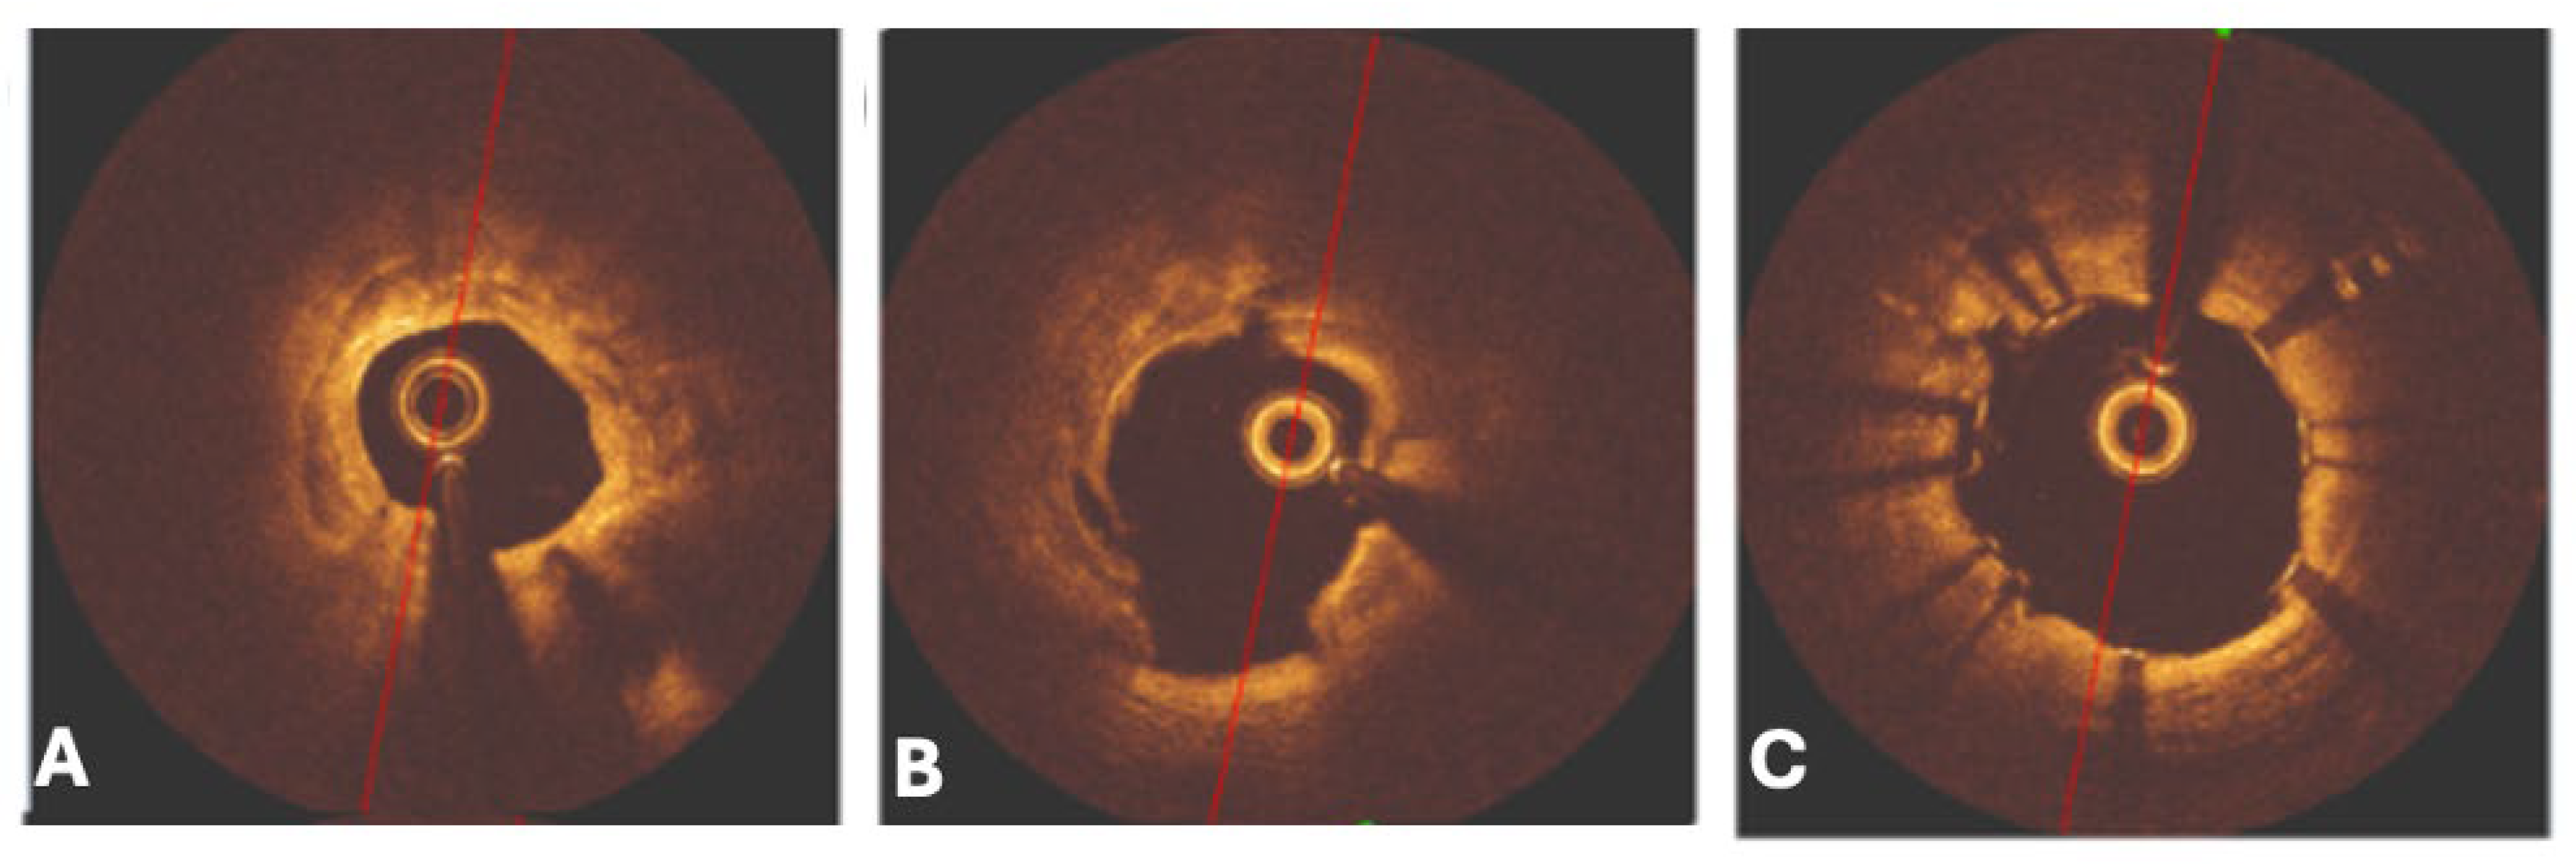

The effective execution and operation of intracoronary imaging modalities during these procedures improve both procedural and long-term clinical outcomes, particularly in intravascular ultrasound (IVUS) (Figure 6 and Figure 7) and optical coherence tomography (OCT) (Figure 8 and Figure 9), where coronary lesion morphology and mapping facilitate better PCI procedural planning [46]. Both IVUS and OCT can detect, localize, and quantify coronary calcification. Notably, OCT can visualize the calcified plaque without producing visual imaging artifacts, thereby minimizing observational scatter, and can evaluate calcium thickness more accurately than IVUS.

Intravascular ultrasound (IVUS) can provide information related to the arc, length, and superficial/deep texture of calcified plaques, but is restricted to the higher capabilities and superiority of optical coherence tomography (OCT), which can provide more than 10 times the spatial resolution of calcium deposits in the coronary walls when compared to the former imaging modality [33]. Both OCT and IVUS have demonstrated that CNs frequently present as eccentric, protruding calcific deposits disrupting luminal geometry. This morphology is associated with difficult wire passage, balloon slippage, and high rates of incomplete stent expansion, all of which translate into increased procedural complexity and suboptimal clinical outcomes [34,35].